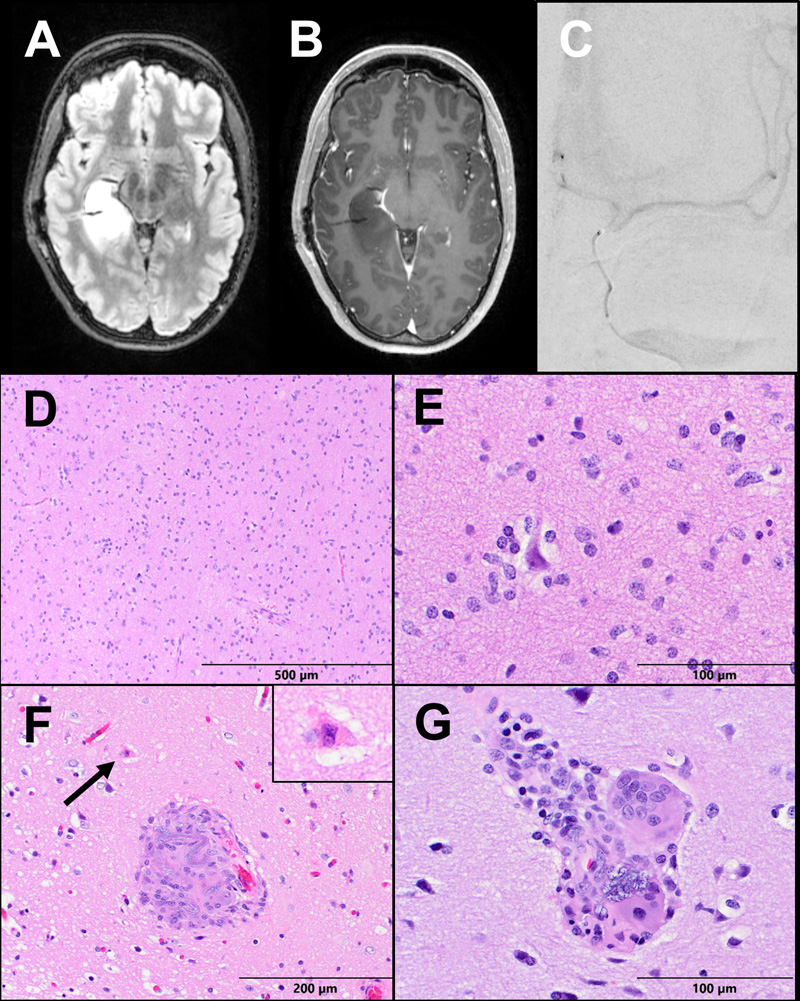

Figure 3: Case 2 Imaging and Pathology. (A) Axial T2-FLAIR and (B) T1 post-contrast MRI brain sequences demonstrate a non-enhancing infiltrative T2 hyperintense mass centered in the right hippocampus and inferior temporal lobe. (C) PA view of a digital subtraction angiogram demonstrates a microcatheter within the left internal carotid artery. (D) The tumor resection shows a moderately cellular glioma infiltrating white matter and (E) cortex with perineuronal satellitosis. (F) A hypereosinophilic ischemic neuron (arrow and inset) is seen next to a vessel occluded by hydrophilic polymer material with associated inflammation. (G) Some vessels contain multinucleate foreign-body giant cells consuming basophilic polymer material.

The patient underwent bilateral Wada testing with the same microcatheterization technique described in Case 1 (Fig. 3c). Injections of both sodium methohexital (Brevital) and amobarbitol (Amytal) were completed, and language representation was identified in the left hemisphere. Three weeks later, the patient underwent right frontotemporal craniotomy for tumor resection. She had an uncomplicated postoperative course and was discharged home on postoperative day 3 at her baseline functional status, with no neurologic deficits. She remains neurologically intact and seizure-free 9 months postoperatively.

Pathology:

Histologic examination of the resection specimen showed a paucicellular infiltrating glioma composed of atypical astrocytes with enlarged, irregular, and hyperchromatic nuclei. No mitoses, necrosis, or microvascular proliferation were detected (Fig. 3d-e). NGS was performed and an IDH1-R132H mutation was identified, along with mutations in TP53, and ATRX. The final diagnosis was diffuse astrocytoma, IDH-mutant, WHO Grade II. Also noted multifocally were a few small parenchymal vessels containing non-polarizable granular blue-gray foreign material consistent with HPE. Surrounding these vessels was foreign-body giant cell reaction, and a few hyper-eosinophilic acutely ischemic neurons (Fig. 3f-g).